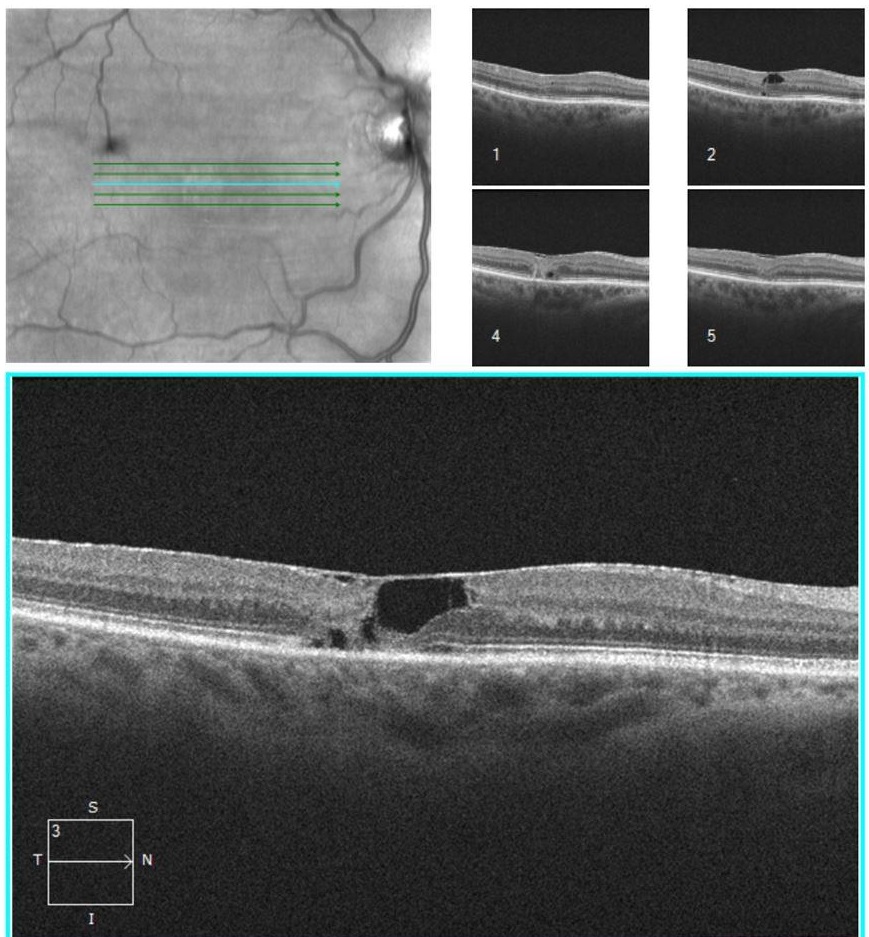

Idiopathic Juxtafoveal Macular Telangiectasia (MacTel), type 2 in a 56 year old female patient. The BCVA was 20/50.

OCT shows areas of cavitations in the inner and outer retina; these are thought to be due to loss of cells creating a void, rather than fluid leakage actively causing

cystic changes. Over time, focal areas of ellipsoid zone loss develop. Those tend to expand overtime.